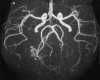

Results: A total of 11 patients with PPV (9 females, 2 males, age range: 7 days to 45 years; mean 11.6 years) were studied. Port wine stain was present in 10 (91%) patients and one patient (9%) had cutis marmorata telangiectatica congenita. Isolated nevi of Ota and Mongolian spots were seen in 4 (36%) patients each. Simultaneous presence of both Mongolian spots and nevus of Ota was present in 1 (9%) patient. The combination of Mongolian spots and bilateral palatal hyper-melanosis was noticed in 2 (18%) patients. Café au lait macule was present in one patient. Bilateral ocular melanosis was found in 3 (27%) patients. Unilateral ocular melanosis was noticed in 4 (36%) patients. Two patients (18%) had history of seizure disorder and intracranial vascular anomalies on MRI imaging. Two patients (18%) had features of Klippel-Trenaunay syndrome. According to the traditional classification, three patients had PPV type 2b, one patient had PPV type 5b, and seven patients had PPV type 2a. According to the Happle's classification, 10 patients had PPV of cesio flammea type, and one patient had PPV of cesio marmorata type.